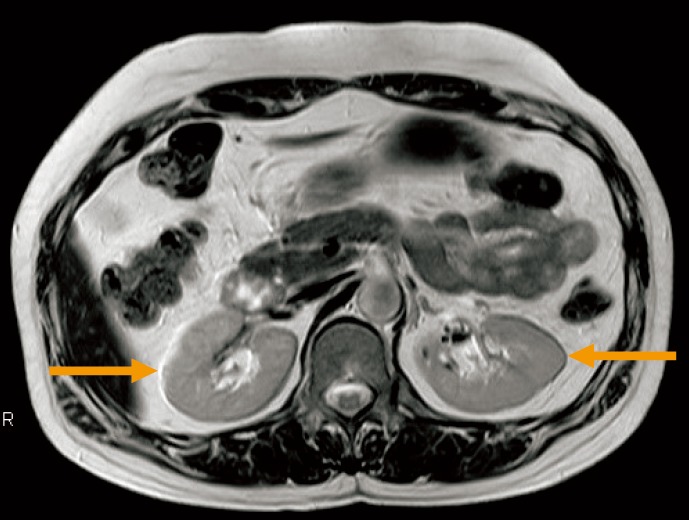

【インボイス制度対応済み】当社では2023年10月からインボイス制度に対応した適格請求書発行事業者番号(通称:T番号・登録番号)を印字した納品書(明細書)を商品に同梱してお送りしております。こちらをご利用いただくことで、税務申告時や確定申告時に消費税額控除を受けることが可能になります。聖隷浜松病院における使用経験 Discovery MR750 を使用した躯幹。アーチファクト例 - 物理的因子 | 画像診断情報サイト Bayer in。どちらのサイトからもご購入可能です。

画像診断 12年1月号 32ー1 特集:MRIアーチファクトの光と影